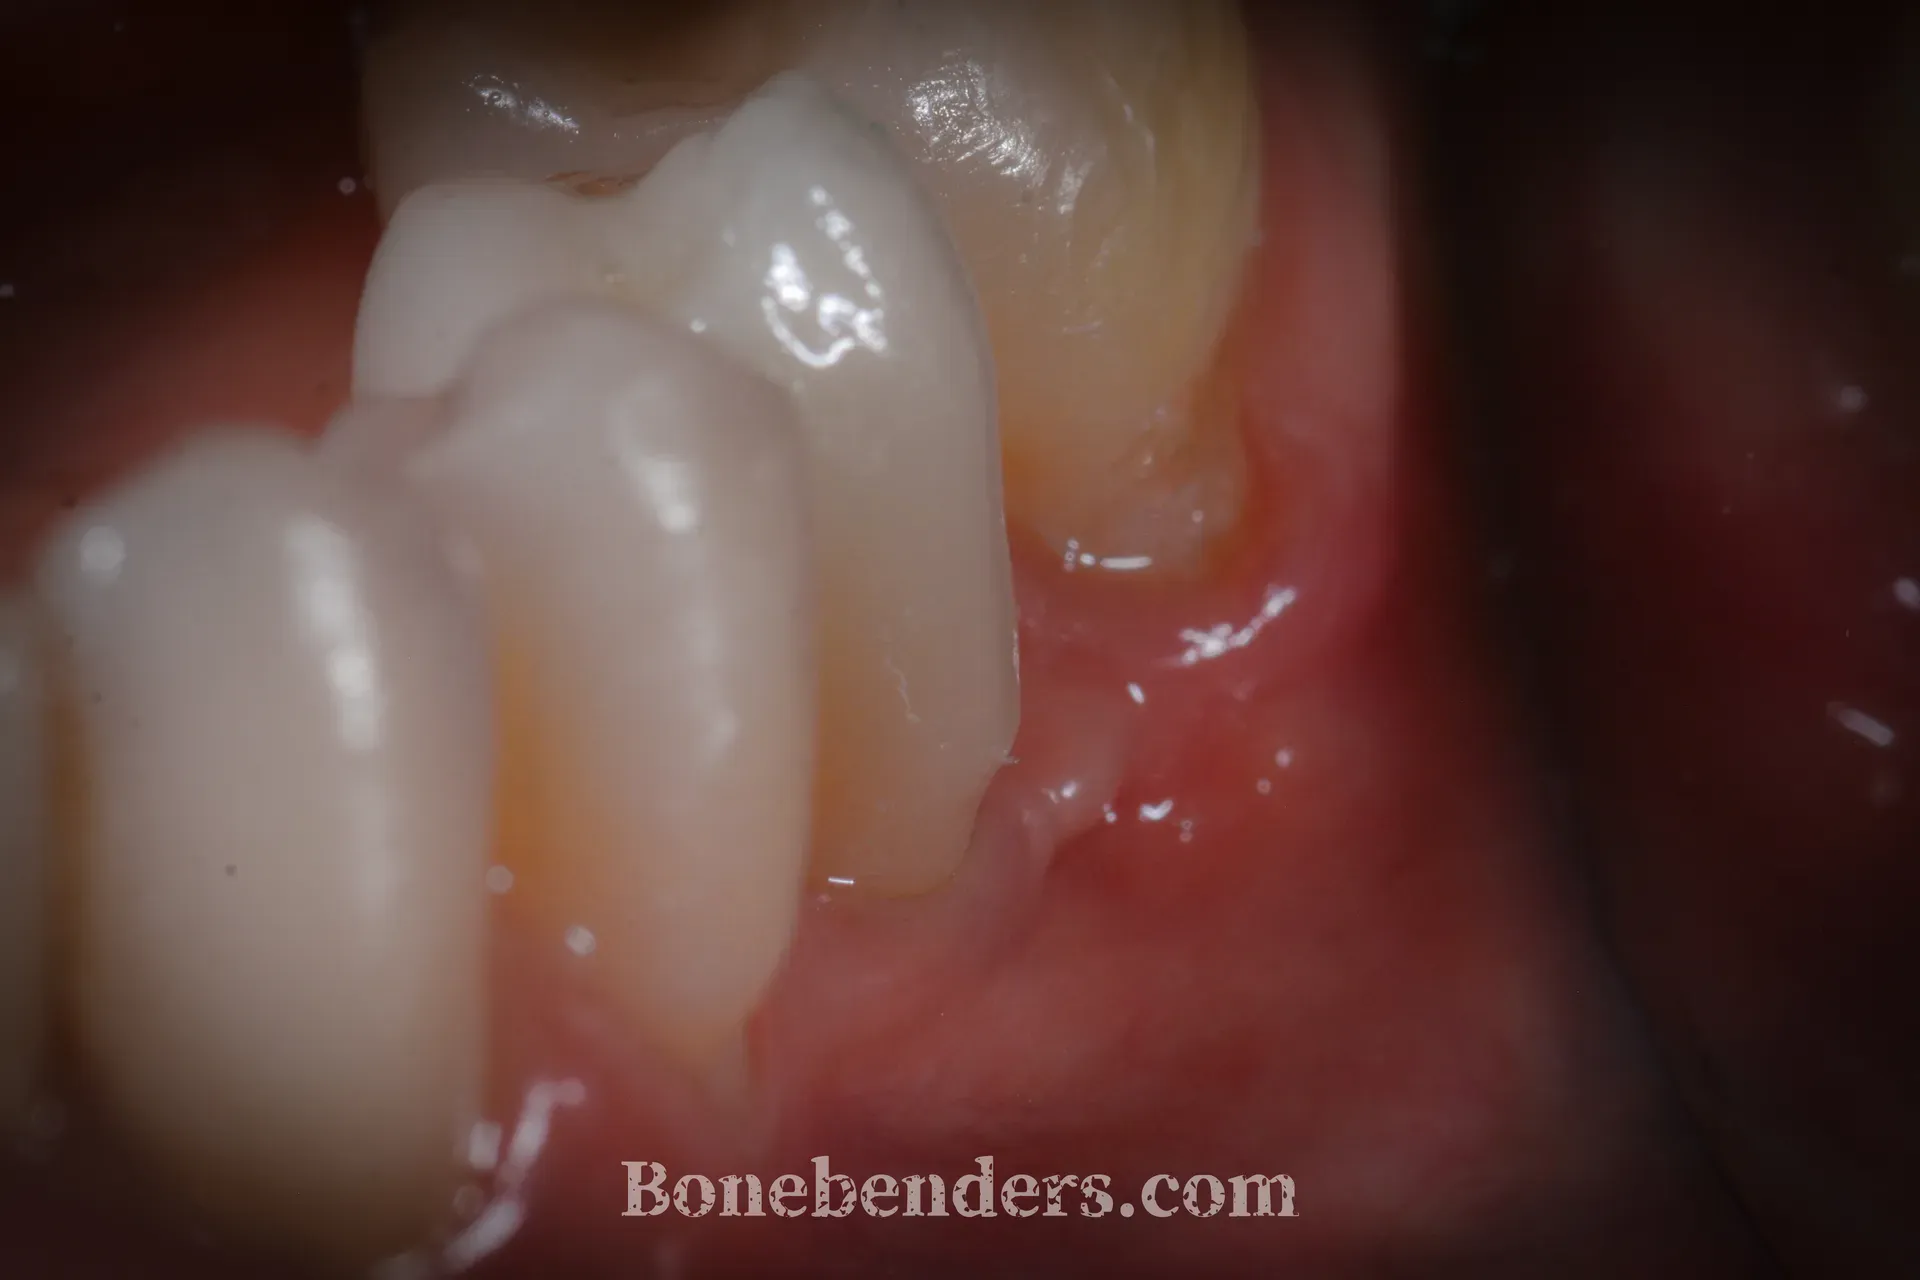

La corona in ceramica definitiva è in funzione. I tessuti molli periimplantari sono stabili, con sondaggio fisiologico su tutti i versanti. L’estetica è salva.